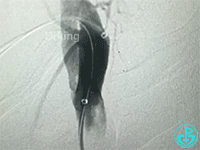

行冠脉造影,从肱动脉开始泥鳅导丝一直在影像中行进。造影结束,病人无不适主诉,返回病区前介入医生例行查看止血夹情况,无意中发现病人右侧颈部较左侧肿大,质软,无疼痛感,略觉胸闷感。立即行彩超检查显示颈部少量积液,右锁骨下动脉及头臂干未发现漏口。行胸部CT可见纵隔血肿,动脉CTA检查疑似头臂干分叉前有渗漏点。

行血管造影检查结果如下:

从影像上看似乎漏口在右锁骨下与右颈动脉分叉近端。